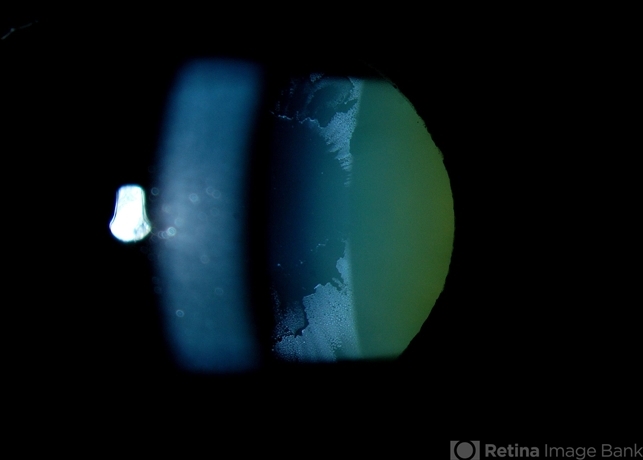

Pseudoexfoliation

pseudoexfoliation glaucoma

Jason Calhoun, Mayo Clinic Jacksonville, Department of Opthalmolgy

Photo slit lamp biomicroscope

Haag Striet Cannon D7

Pseudoexfoliation syndrome on the lens.